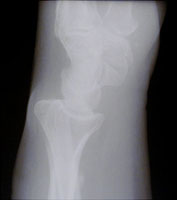

- Click on the image for a larger versionBLateral radiograph of the wrist. Neither fracture is well seen.